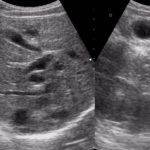

- УЗИ простой и информативный метод, который покажет наличие кист, их локализацию, количество и размеры.

- Ультразвуковое исследование: позволяет обнаружить в печени кистоподобную структуру при однокамерном эхинококкозе или четко очерченное гиперэхогенное очаговое поражение печени при многокамерном эхинококкозе.